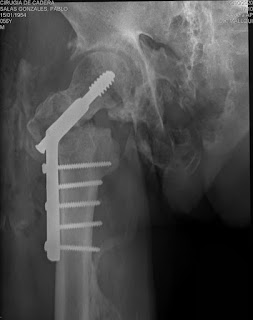

Hace 12 días el matador de toros Pablo Salas G. en una tienta en un lugar de Cerro de Pasco sufre caída del caballo lo que produce fractura transtocanterea del fémur derecho por lo que es trasladado a la ciudad de Lima siendo atendido por el Dr. Cesar Baltazar.

Después de unos días de tratamiento es intervenido hoy día (ayer) quirúrgicamente en la Clínica Universitaria por los traumatólogos Dr. Lynn Mallqui, Dr. Alfredo Bueno y Arturo Arbildo del Staff del Hospital Nacional "Sergio E. Bernales" logrando reducir la fractura mediante colocación de tornillos de placa DHS.